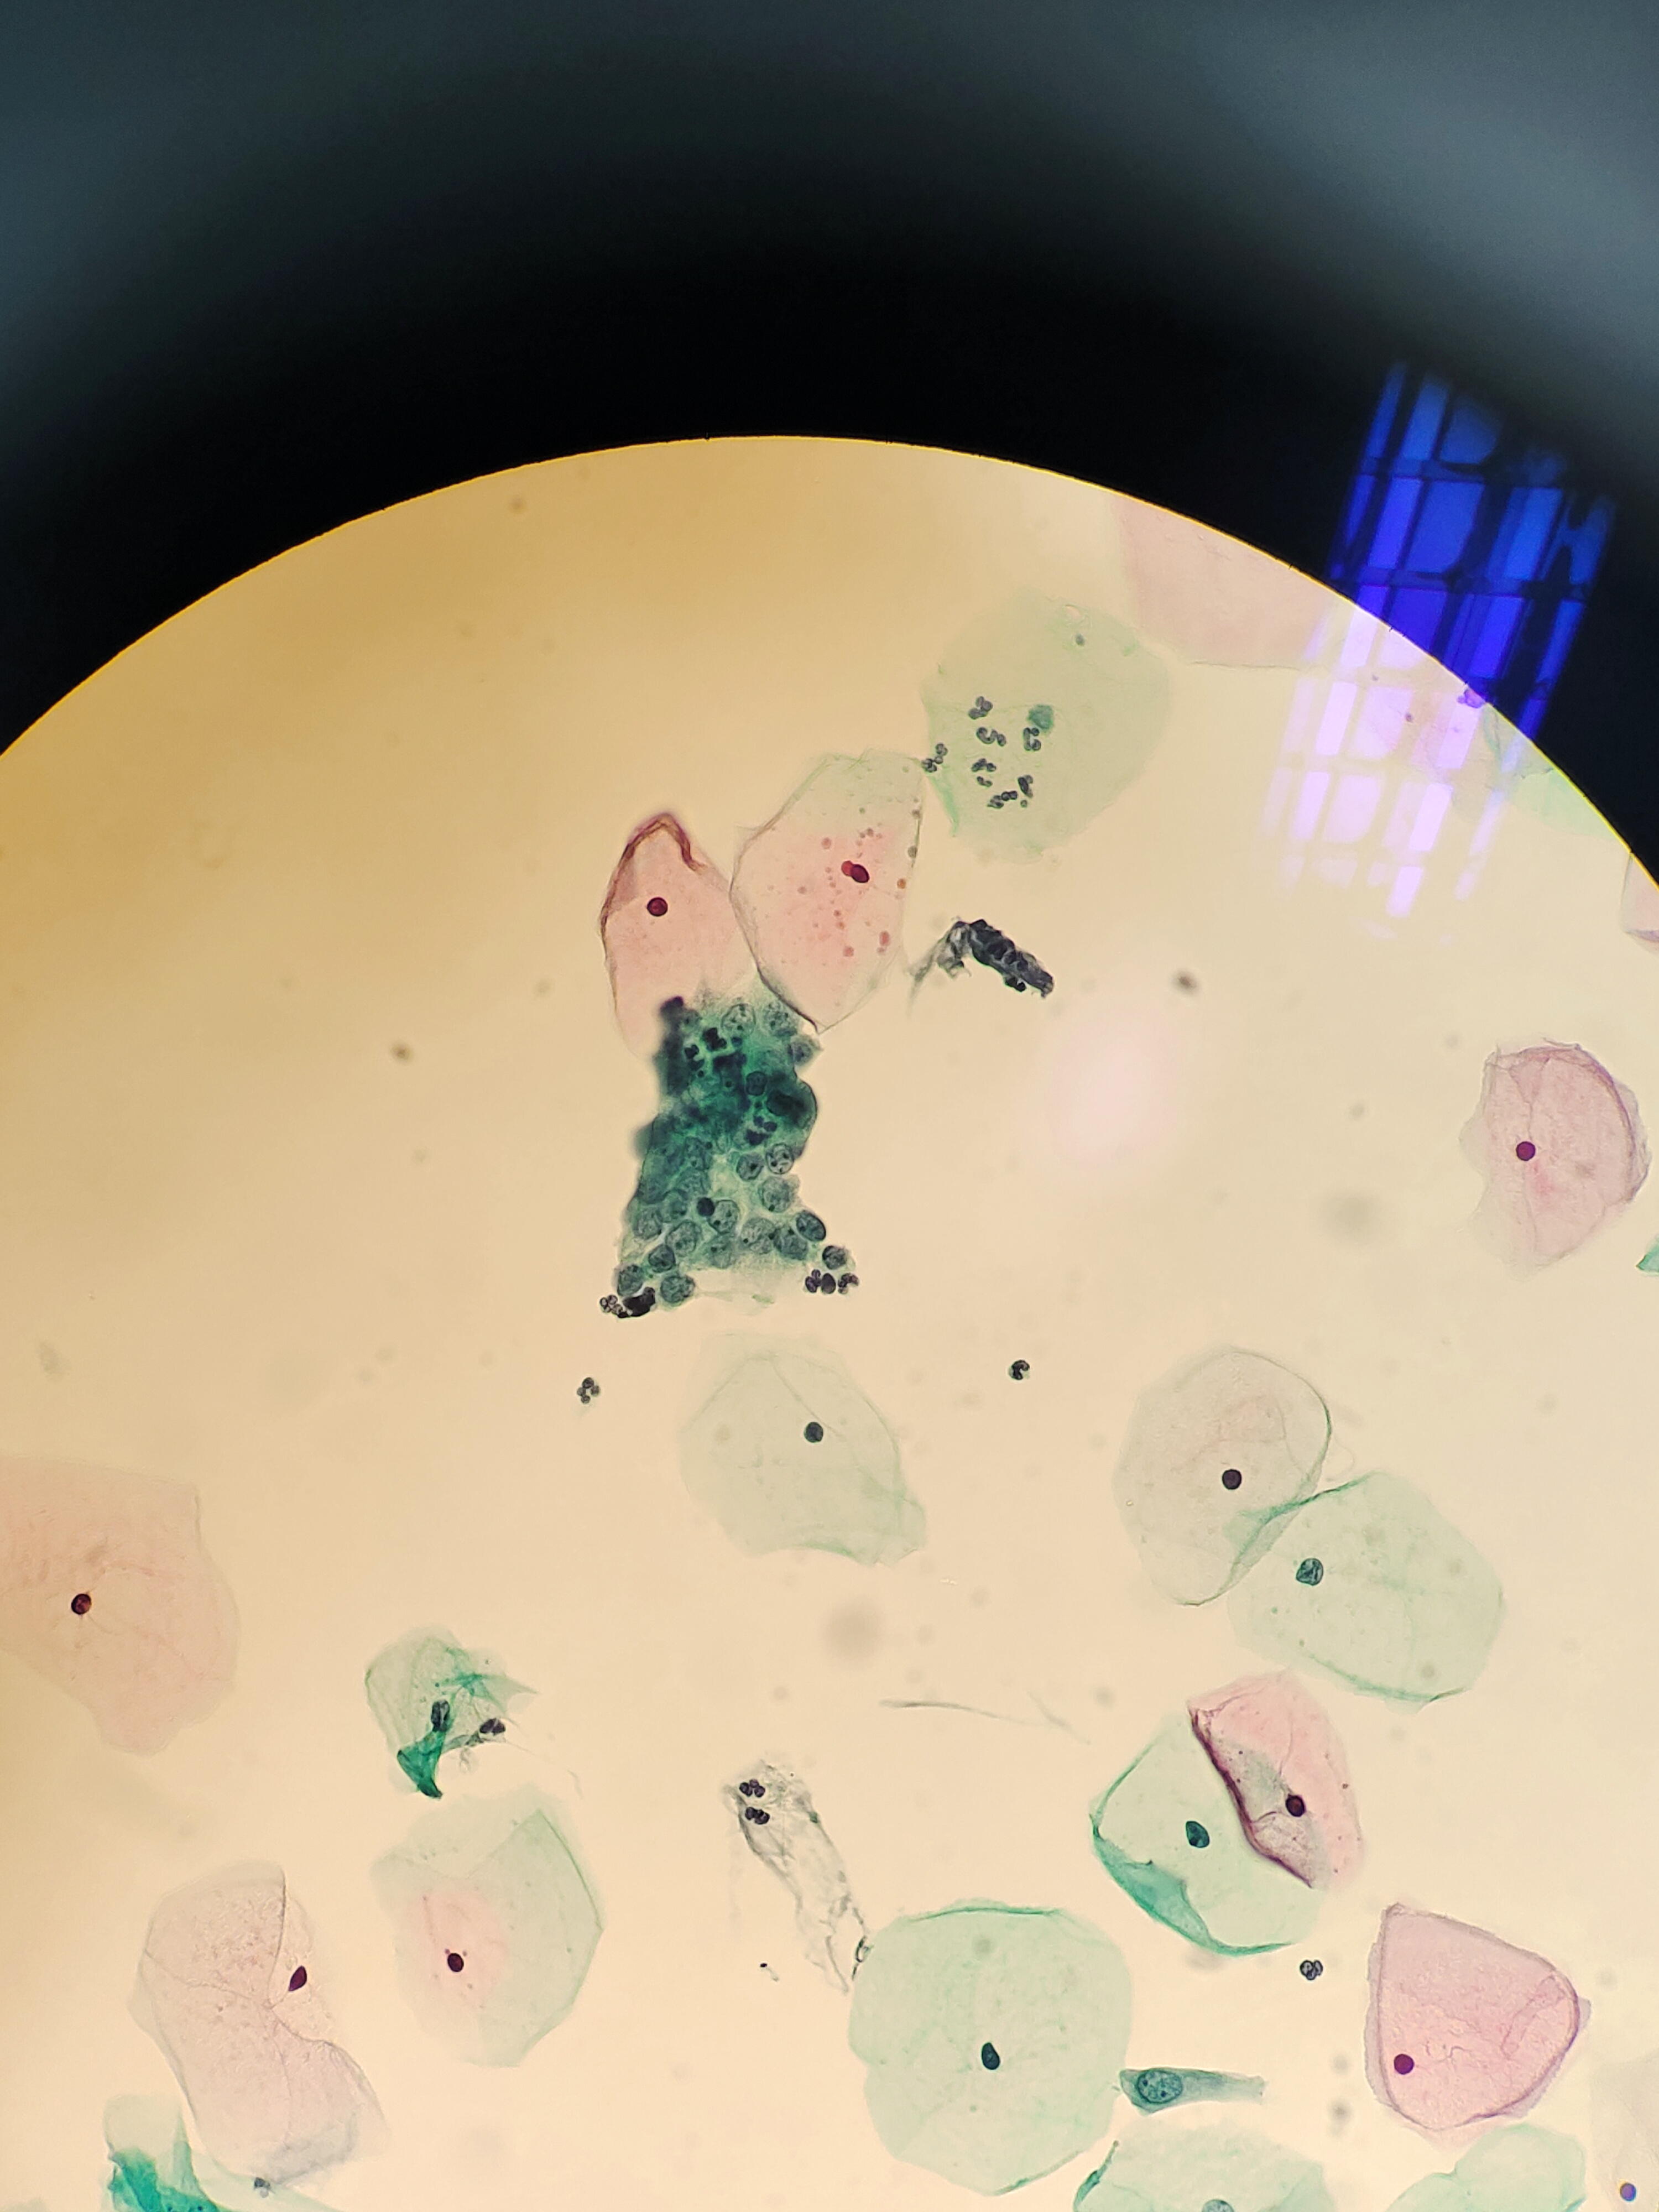

月经过后7天,下腹痛伴阴道少量血性分泌物,宫颈肥大、糜烂、触血。HPV阴性。老师们,成团细胞,有些核大,有事吗?

宫颈

液基

巴氏

图1

NILM